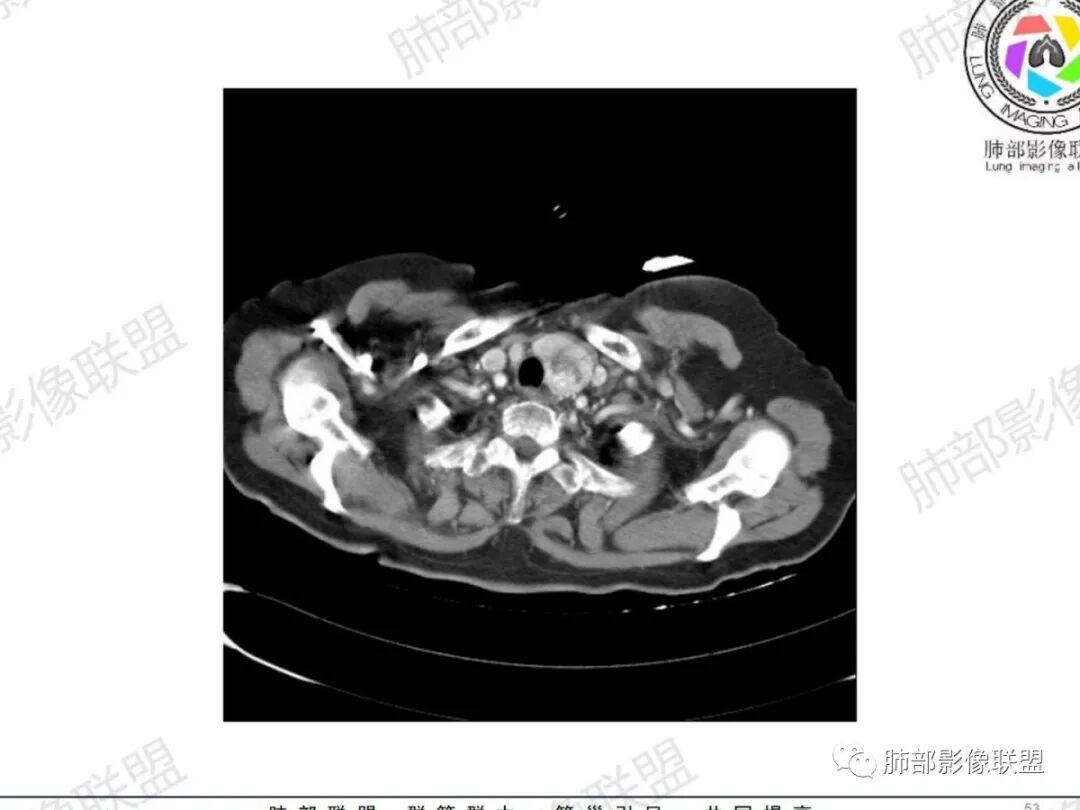

主支气管后缘外可见一实性结节,病变跨支气管管壁生长,部分突向管腔内,病变边缘光滑,平扫密度均匀,增强后尚均匀强化,纵隔淋巴结肿大不明显。

气管右后侧壁结节,结节向气管腔内突出,气管壁增厚,轻度强化,左侧甲状腺占位,考虑气管原发肿瘤,腺样囊性癌?类癌?

女,69反复咳嗽1年,胸闷二天,气管腔内见结节影,病灶突向腔内,管腔狭窄受压呈月牙状改变,增强扫描轻度强化,考虑腺癌?左侧甲状腺病变,不除外转移性病变。

气管右后壁占位,平扫密度稍低于肌肉

增强后与肌肉类似,部分强于肌肉,提示强化

内外边缘光滑

宽基底与气管相连

附近壁增厚

前方见一小淋巴结,后内侧与食道联系很紧